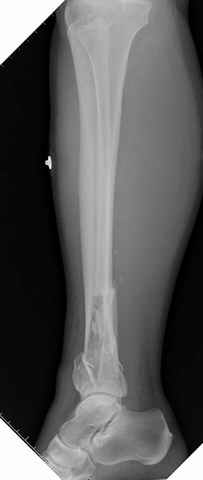

На снимках варианты фиксации малоберцовой:

№ 2-5 при огнестрельном переломе